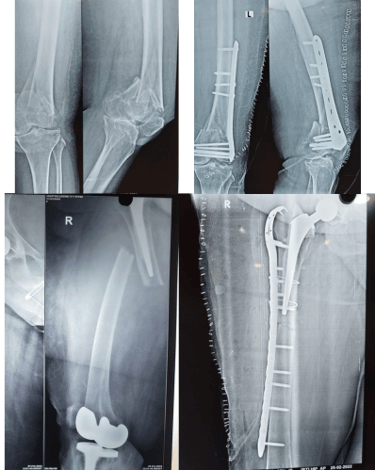

Sivam Hospital – Advanced Knee Replacement in Chennai

At Sivam Hospital, we specialize in advanced joint replacement surgeries to relieve pain, restore mobility, and enhance quality of life. Our expert orthopedic team uses modern techniques and state-of-the-art facilities to ensure safe procedures and faster recovery.

Knee Replacement – Effective treatment for severe Osteoarthritis, Rheumatoid arthritis, secondary arthritis, inflammatory arthritis and joint damage helping patients regain pain-free movement.

Uni Knee Replacement – A minimally invasive partial knee replacement procedure that preserves healthyportion of the joint and tissue while ensuring quicker recovery.

Total Knee Replacement (TKR) – Comprehensive surgical care to replace the entire knee joint, offering lasting pain relief, deformity correction, improved gait and function.

Revision Total Knee Replacement– Specialized surgery to correct or replace the failed knee implants due to infection or trauma restoring stability and improving function.

Sivam Hospital – Advanced Hip

Replacement In Chennai

At Sivam Hospital, we specialize in geriatric orthopedics, providing comprehensive care for bone and joint problems in elderly patients. Our orthopedic experts focus on treating age-related conditions such as fractures, arthritis, osteoporosis, and joint degeneration with safe and effective techniques.

We deliver personalized treatment from diagnosis to rehabilitation, making Sivam Hospital a trusted choice for elderly orthopedic care. With advanced facilities, minimally invasive options, and dedicated physiotherapy support, we ensure better mobility, reduced pain, and improved quality of life for senior patients.